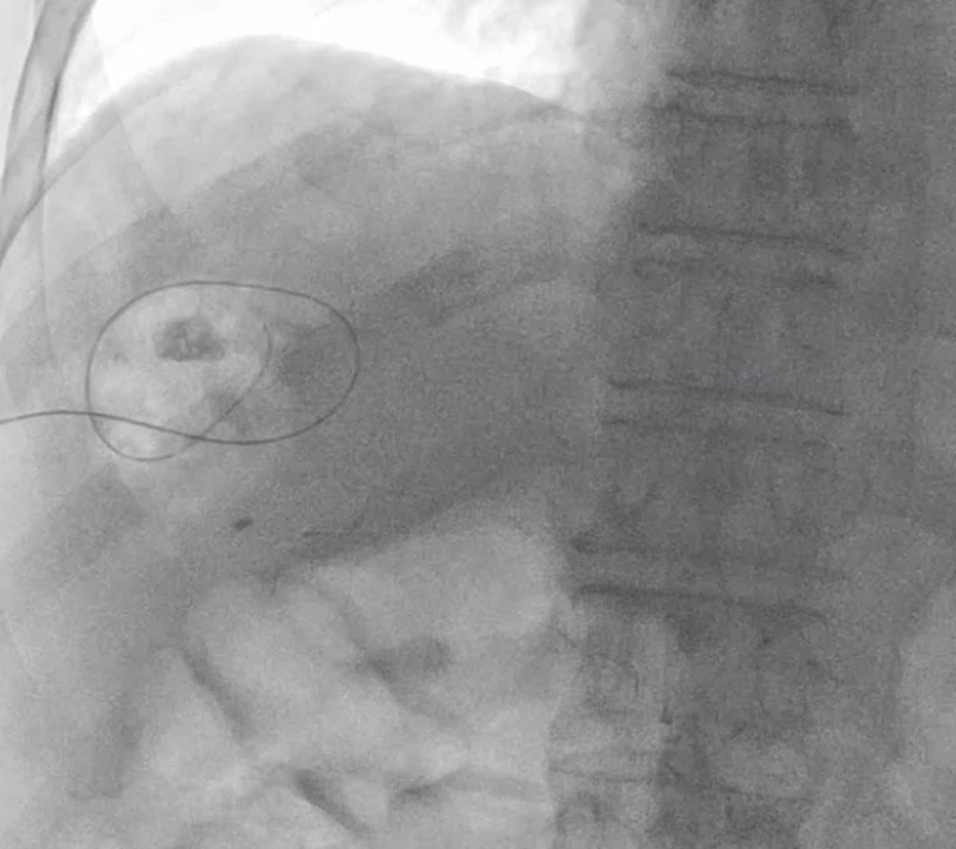

잘 들어갔다는 게 확인되면 아주 가느다란 철사를 넣습니다. 이 철사의 이름은 hair wire 입니다. 마치 머리카락 처럼 가느다랗기 때문이죠.

hair wire 를 넣은 뒤에는 introducer sheath 그 다음엔 앞서 말한 hair wire 보다 조금 굵은 철사가 들어갑니다.

마지막으로 굵은 철사를 따라 배액관이 들어갑니다.

배액관의 사이즈는 꽤 크므로 (최소 3mm 굵기) 이 과정에서 통증을 호소하시는 분들이 많습니다.